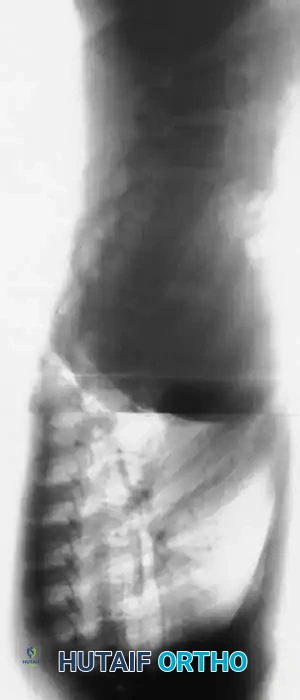

Fig. 38-202: Postoperative radiographs demonstrating anterior fusion with vascularized rib graft and structural strut grafting in a patient with severe dystrophic kyphoscoliosis.

For smaller dystrophic kyphoscoliosis (kyphosis <40 degrees), posterior instrumentation and arthrodesis may be attempted early, but the fusion mass must be explored at 6 to 12 months. If kyphosis exceeds 50 degrees, the combined anterior/posterior approach is non-negotiable. The anterior fusion must extend one or two levels beyond the end vertebrae of the kyphotic segment to prevent junctional failure.